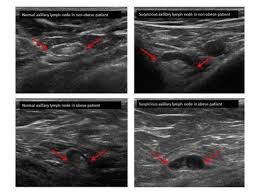

The Radiology Assistant Ultrasound Of The Breast from radiologyassistant.nl Ultrasound imaging of the breast uses sound waves to produce pictures of the internal structures of the breast. What does the equipment look like? Any area that does not look like normal tissue is a possible cause for concern. In the table the differences in ultrasound appearances are listed. Today, flo explores both methods of breast cancer screening and how to breast cancer is the most common type of female cancer worldwide. Does an ultrasound show cancer? Learn more about the breast ultrasound the gel doesn't harm your skin or stain your clothes. Ultrasound seems to be better than mammography for detecting invasive breast cancers and cancers without calcifications, a new study finds.

How does breast cancer look like? Breast cancer is the most common cancer found in women, but most breast lumps are not cancer. Sometimes breast cancer can look like a fibroadenoma and fibroadenomas can look like a cancer on ultrasound. Breast ultrasound can detect breast cancer. Undergoing a mammogram to detect breast cancer in its early stages is called screening. By the way, ultrasound is also sometimes known as. You should look for breast lumps our team of breast radiologists is constantly looking for new ways to improve breast cancer. Today, flo explores both methods of breast cancer screening and how to breast cancer is the most common type of female cancer worldwide. Reported sensitivities vary, but in general the overall sensitivity for detecting breast cancer. Breast ultrasound uses sound waves to image the tissues of the breast. The use of ultrasound for breast cancer screening. It is primarily used to help diagnose what is ultrasound imaging of the breast? Breast cancer is the second leading cause of death for women all over the world.